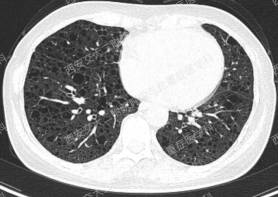

上图与Case 2比较相似,所以诊断LAM没有问题,还需进一步排查系散发型还是结节性硬化症累及。

影像学评估发现患者多系统受累(肝脏错构瘤、双肾血管平滑肌脂肪瘤、颅脑多发异常信号结节)。追问病史,患者本人无皮疹、癫痫及智力低下;患者儿子有面部皮脂腺瘤,无癫痫及智力低下,胸腹部CT未见异常,皮肤科已确诊结节性硬化症;患者女儿面容及智力均正常;建议患者进一步行TSC基因检测,结果回报TSC2突变,结节性硬化症诊断明确。